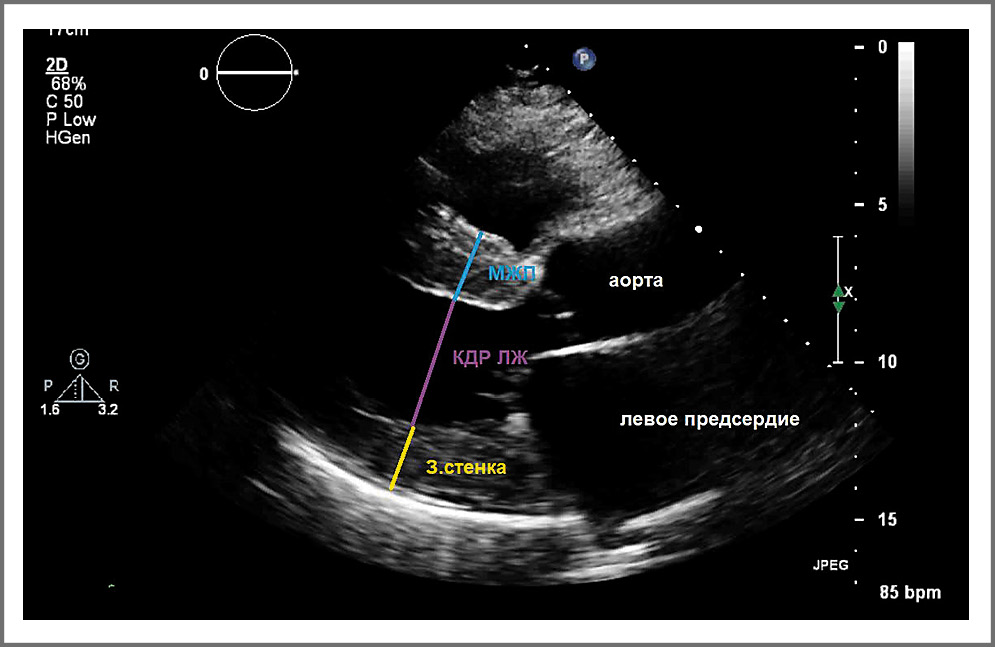

При измерении из парастернального доступа в позиции по длинной оси ЛЖ необходимо оценить соотношение поперечного размера аорты и ЛП, толщину межжелудочковой перегородки, конечно-диастолический и конечно-систолический размеры ЛЖ, толщину задней стенки (рис. 2). Измерение толщины межжелудочковой перегородки может быть затруднено из-за таких структур ПЖ, как трабекулы, наджелудочковый гребень и модераторный пучок. Толщина стенки может быть проверена дополнительно в парастернальной позиции по короткой оси (рис. 3).

Рис. 2. Оценка структур из парастернального доступа в позиции по длинной оси ЛЖ.